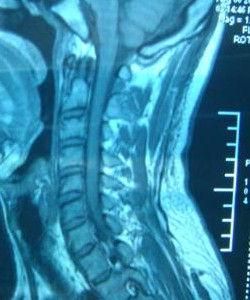

椎間盤脫出

此種情況比較少見,在骨科所做的椎間盤手術中大約占2%左右。因椎間盤已經脫入椎管,已沒有通過非手術療法回位的可能。此種病症的治療方法只有一個,就是手術取出。

椎間盤突出

椎間盤膨出

理論上來講膨出是較突出輕微,此症主要是腰肌緊張,椎間盤受擠壓力量過重所致。用正骨、按摩法解除腰肌緊張即可治癒。在一般的情況下經過二至四周可慢慢恢復。